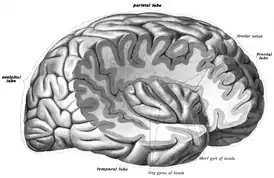

Центральная островковая борозда (лат. sulcus centralis insulae) делит долю на две части: большую переднюю и меньшую заднюю. Большой участок коры, покрывающий островок сверху и латерально, образует крышечку (лат. pars opercularis) и формируются из части прилегающих лобной, височной и теменной долей. Передняя часть центральной доли разделена на три или четыре коротких извилины, а задняя сформирована длинными извилинами.

Дополнительные изображения

Островок левого полушария

Фронтальный разрез головного мозга через третий желудочек

Фронтальный разрез через фронтальный рог боковых желудочков

Фронтальный разрез через переднюю спайку.

Глазная поверхность левой лобной доли

Верхняя поверхность височной доли

Горизонтальный разрез левого полушария